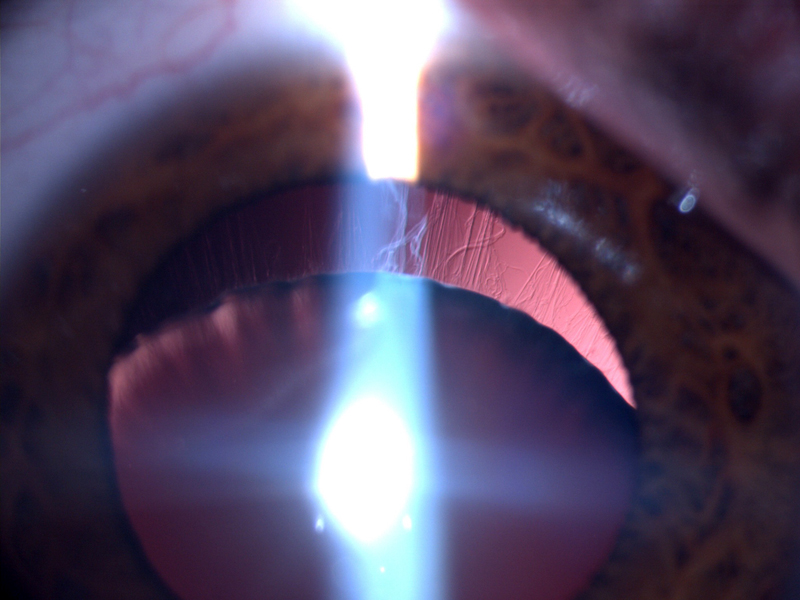

Niña de 13 años, con 49,4kg de peso, 1,63 m de talla y 18,59 kg/m2 de índice de masa corporal. Derivada por el pediatra para valoración oftalmológica, por antecedentes familiares de homocistinuria (hermano) y sospecha de Síndrome de Marfan (hermana). A la exploración física se destaca el aspecto marfanoide y se objetiva una agudeza visual corregida (OD: 160°-3.50-9.25; OI: 180°-3.50-9.25) de 0,6 en ambos ojos. En lámpara de hendidura se observa una subluxación inferior del cristalino bilateral y fondo de ojo dentro de la normalidad.1. ¿Cuál es la primera sospecha diagnóstica?

La luxación o ectopia del cristalino, es el signo oftalmológico más llamativo y está presente en aproximadamente un tercio de los pacientes en la primera década de la vida y en más del 90% de los pacientes en la tercera década1,2.Se define por el desplazamiento del mismo, normalmente hacia inferior nasal de forma simétrica, como resultado de la degeneración y rotura de las fibras de la zónula. Esto puede provocar disminución de la agudeza visual o incluso glaucoma agudo secundario2. La fibrilina-1 (glucoproteína secretada en la matriz extracelular) es uno de los componentes más importantes de las fibras zonulares del cristalino con proteínas ricas en cisteína. En la homocistinuria la estructura de la fibrilina se altera por la reducción de uniones disulfuro en la C-terminal de la fibrilina-13.

La intervención quirúrgica en pacientes con homocistinuria se asocia a un alto riesgo de complicaciones, entre ellas, el prolapso de vítreo y el desprendimiento de retina. Por esta razón, no se suele intervenir si la agudeza visual es buena y no están presentes otras complicaciones derivadas de la subluxación del cristalino1.